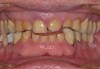

A 76-year-old, retired businessman presented to the office to improve his smile and overall oral health (Figure 1). An esthetic assessment revealed minimal display of the upper anterior teeth and dark discoloration of all teeth (Figure 2). Cephalometric analysis determined that the ANB measurement was 4°, indicating a mild Class II skeletal pattern with upright and retroclined incisors. At 145°, the interincisal angle was excessive, and at 6°, the 1-NA measurement was less than ideal (ie, 22°). If the root angulation of the upper incisors could be shifted toward the palate, it would improve the display and function of the upper anterior teeth with less restrictive anterior guidance (Figure 3).

A more comprehensive examination determined that the patient's anterior teeth bite in an end-to-end relationship with a wide area of contact, which resulted in moderate to locally severe anterior dental wear. Possible crossover bruxing with a flat lower incisor wear table was noted. In the absence of orthodontics, supraeruption of the worn teeth contributes to a poor prognosis for conservative restoration without crown lengthening and gingival reduction. Additional findings included an undersized mesial-distal width of the upper and lower anterior teeth with reduction in the dental arch perimeter; missing teeth Nos. 19 and 30 with distal drift of Nos. 20 and 21, leaving space distal of No. 22; a fixed bridge restoration for tooth No. 19 and an implant fixture in the tooth No. 30 site, both requiring repair; and some concern regarding inadequate oral hygiene.

(2.) Pre-treatment anterior bite.

Figure 2